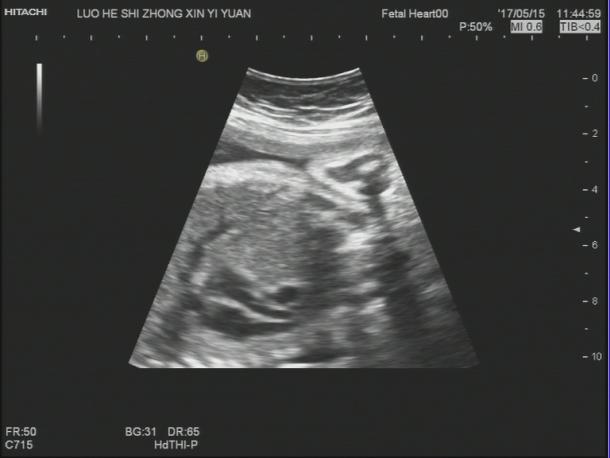

【声像图表现】 胎儿心脏:四腔心切面可显示,左心偏小,右心偏大.主动脉内径明显偏细,PA:7.1mm,PAV:84cm/s,AO:4.0mm,AOV:38cm/s,因体位限制,主动脉弓显示不清。胎儿腹部内脏:胆囊位于腹腔左侧,心脏及胃泡位于右侧胸腔,心房反位,心室左襻,肺动脉发自功能右室,主动脉发自功能左室,三尖瓣增厚,回声增强,四腔心切面可显示.左心明显偏小,右心明显扩大。因胎儿体积大位置较远,左房明显小,未探及明显的肺静脉血流信号入左房。

32周的孕妇,这次超声检查是发现胎儿肝脏,胆囊位于腹腔左侧,心脏及胃泡位于右侧胸腹腔,理论上胎儿肝脏、胆囊应位于腹腔右侧,胃泡位于腹腔左侧,心脏位于胸腔偏左侧,但是这个胎儿不仅存在着脏器反位,而且从声像图来看胃泡和心脏位于一个切面,难以分清是在胸腔还是腹腔。根据超声资料,胎儿心脏还表现左心偏小,右心偏大.主动脉内径明显偏细,因体位限制,主动脉弓显示不清。因胎儿体积大位置较远,左房明显小,未探及明显的肺静脉血流信号入左房,说明胎儿心脏也存在发育不良。

正常膈肌的超声声像图表现为:紧贴肺及心脏下缘、肝脏上缘的薄带状低回声,位于胸腹腔之间,明显向胸腔突出的圆顶状结构。但是在这个患者的声像图里我们并没有找到这样的结构,后来患者去了上级医院复查,也证实了我们的诊断:胃泡位于胸腔(考虑膈疝);右位心。一般来说膈疝是膈的发育缺陷导致腹腔内容物疝入胸腔,膈疝特征性超声声像图包括:腹围较正常偏小,胸腔内出现移位的胃泡、有蠕动的囊性结构、存在血供来自肝脏实性占位等,心脏轴线偏移,无膈肌超声声像图等。当发现心脏轴线移位时要注意排除胸内致病因素,需注意与肺囊腺瘤、肺囊肿、肺肿瘤、隔离肺、支气管囊肿、一侧胸腔积液、膈膨升等鉴别。与膈疝最容易混淆的是先天性肺囊腺瘤畸形,先天性肺囊腺瘤畸形的囊腔大小相对稳定,短时间内不会有变化,而膈疝的胃肠结构在短时间内会有蠕动,会有变化。另外还应特别注意膈膨升,膈膨升于矢状切面上能观察到膈肌呈弧形低回声分隔胸腹腔,但膈肌水平明显高于肋弓水平。